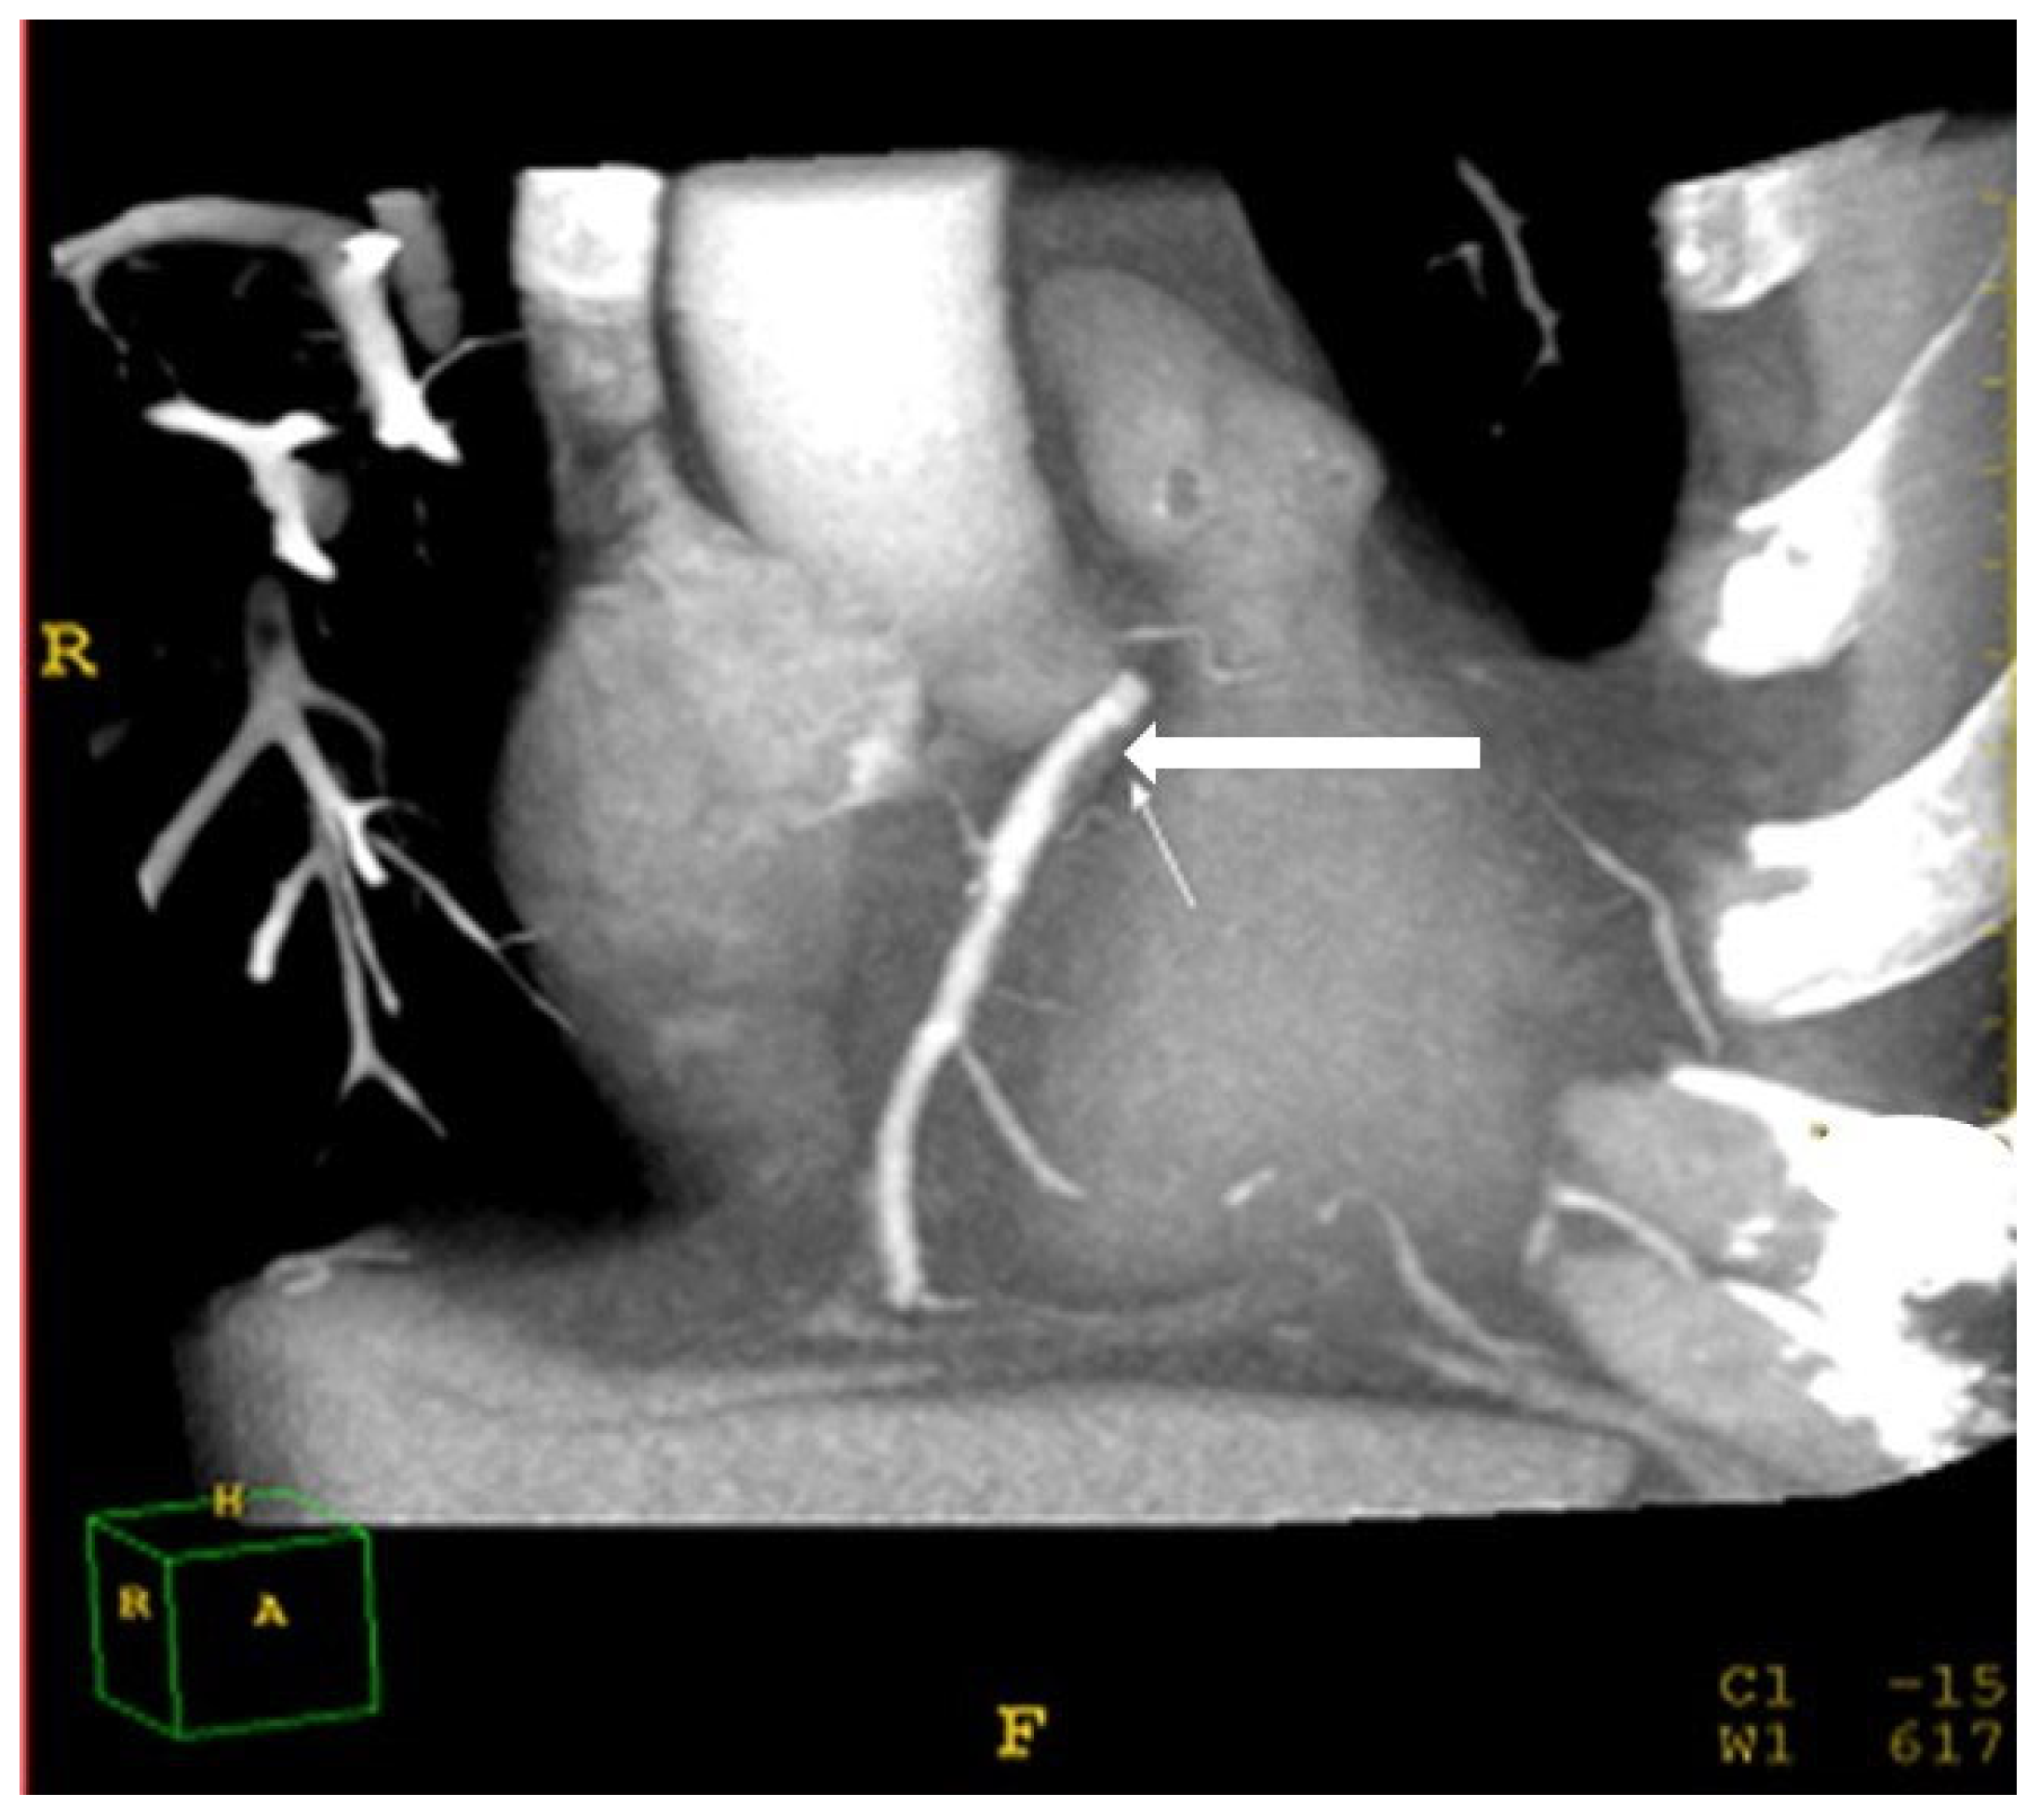

2.7. Assessment of Coronary Atherosclerosis

| Coronary soft plaques (% of total) | 38 | 50 | 25 | 0.001 |

| CAD: stenosis > 50% (% of total) | 22 | 30 | 11 | 0.001 |

| Diffuse fatty liver (LD-SD > −10HU) | 2.75 | 2.3–4.9 | 0.001 |

| Excessive visceral fat (>330 cm2) | 2.01 | 1.2–3.8 | 0.001 |